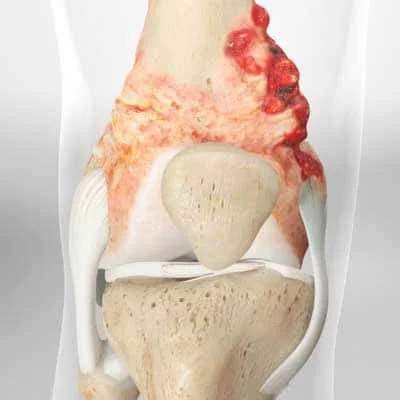

There are various types of bone cancer, each with their own set of symptoms and treatment options. Osteosarcoma is the most common type of bone cancer, affecting the long bones of the arms and legs. Chondrosarcoma, Ewing's sarcoma, and giant cell tumour are other types of bone cancer.

Chondrosarcoma is a bone cancer that develops from cartilage cells. It is the second most common type of bone cancer, accounting for approximately one in every four cases. Chondrosarcoma is most common in adults over the age of 40. Chondrosarcoma is typically treated with surgery to remove the tumour, followed by radiation therapy or chemotherapy.